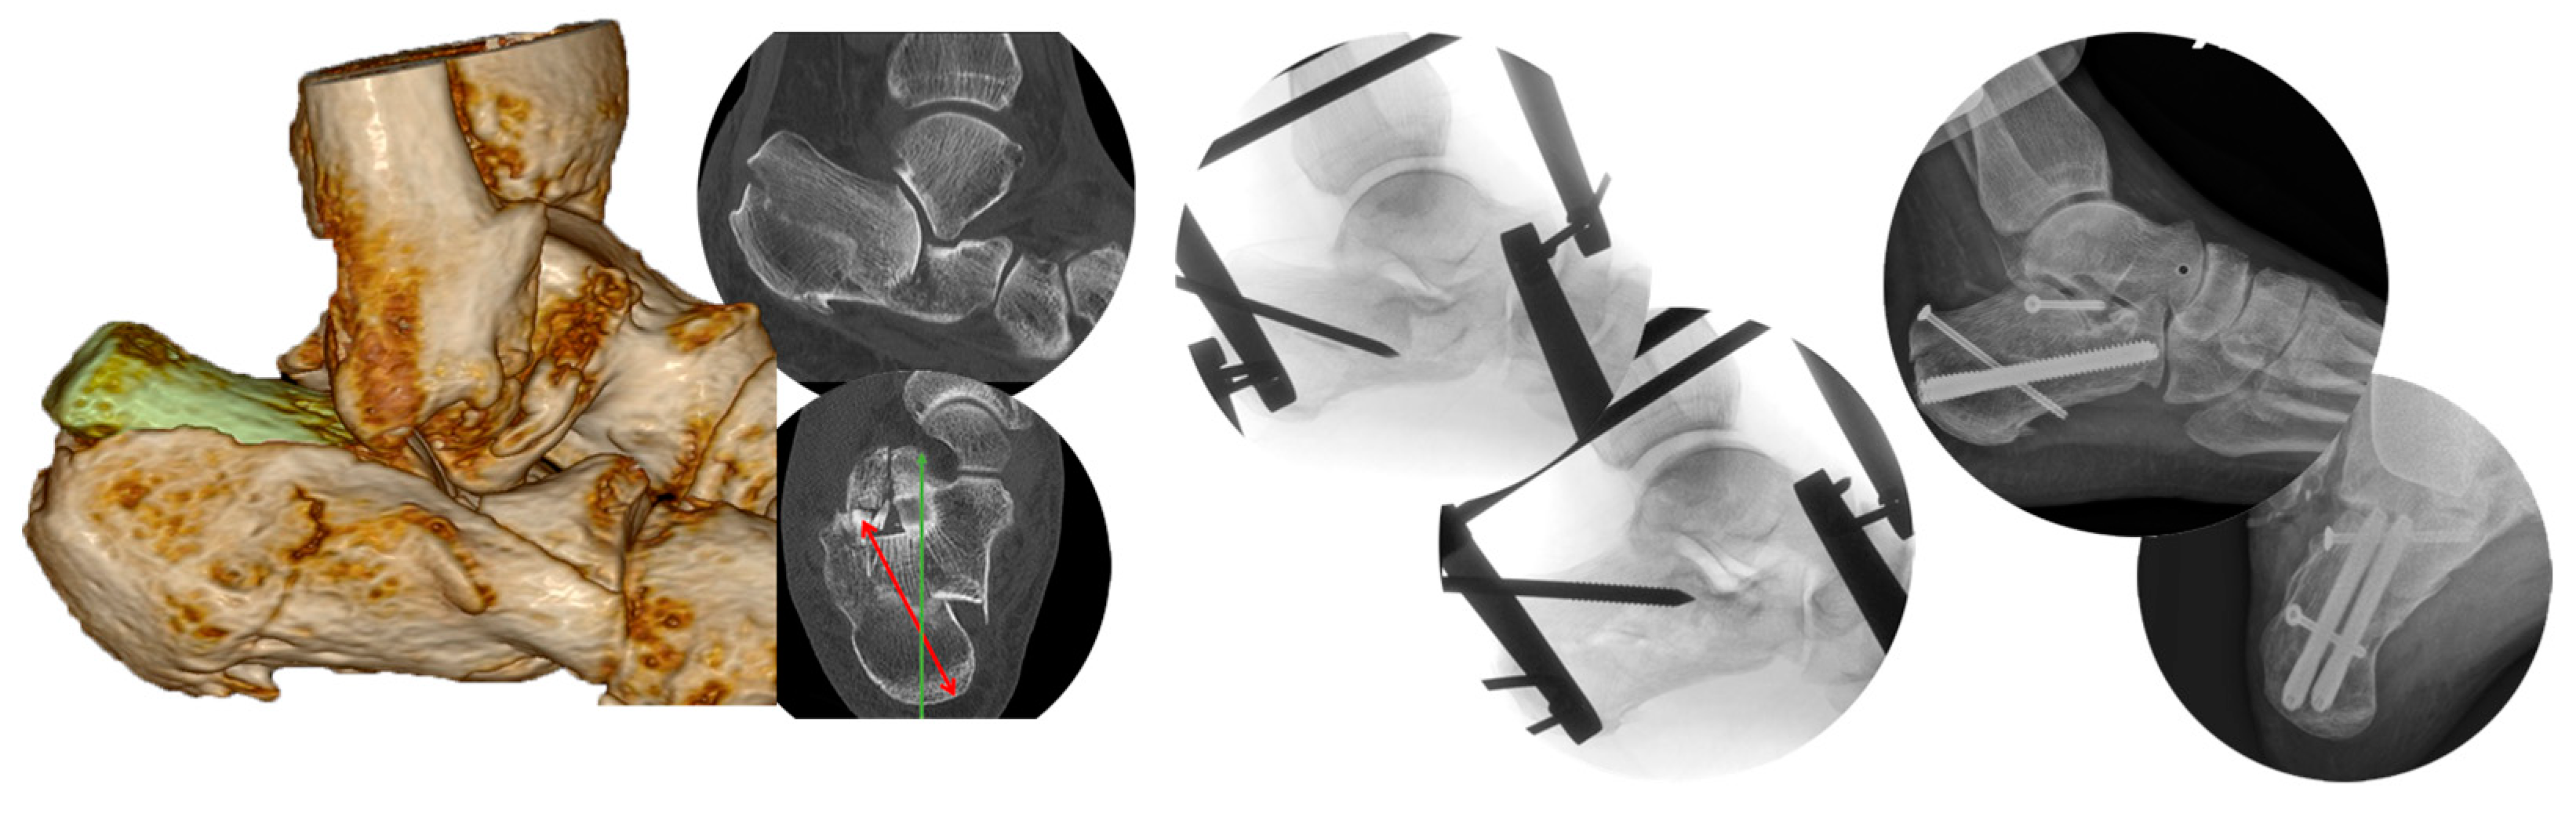

2.4. Method